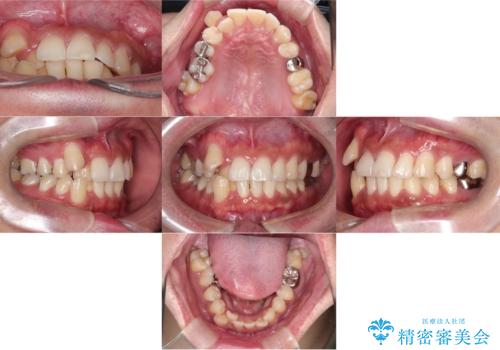

【ワイヤー矯正】八重歯と下の歯の凸凹を治したい

- 主訴:右上の八重歯と、下の歯の凸凹を治したい

上顎右側第一小臼歯と下顎右側第一小臼歯を抜歯しワイヤー矯正を行いました。

右側2級、左側1関係だったため、右側上下第一小臼歯を抜歯し、ワイヤー矯正を行いました。